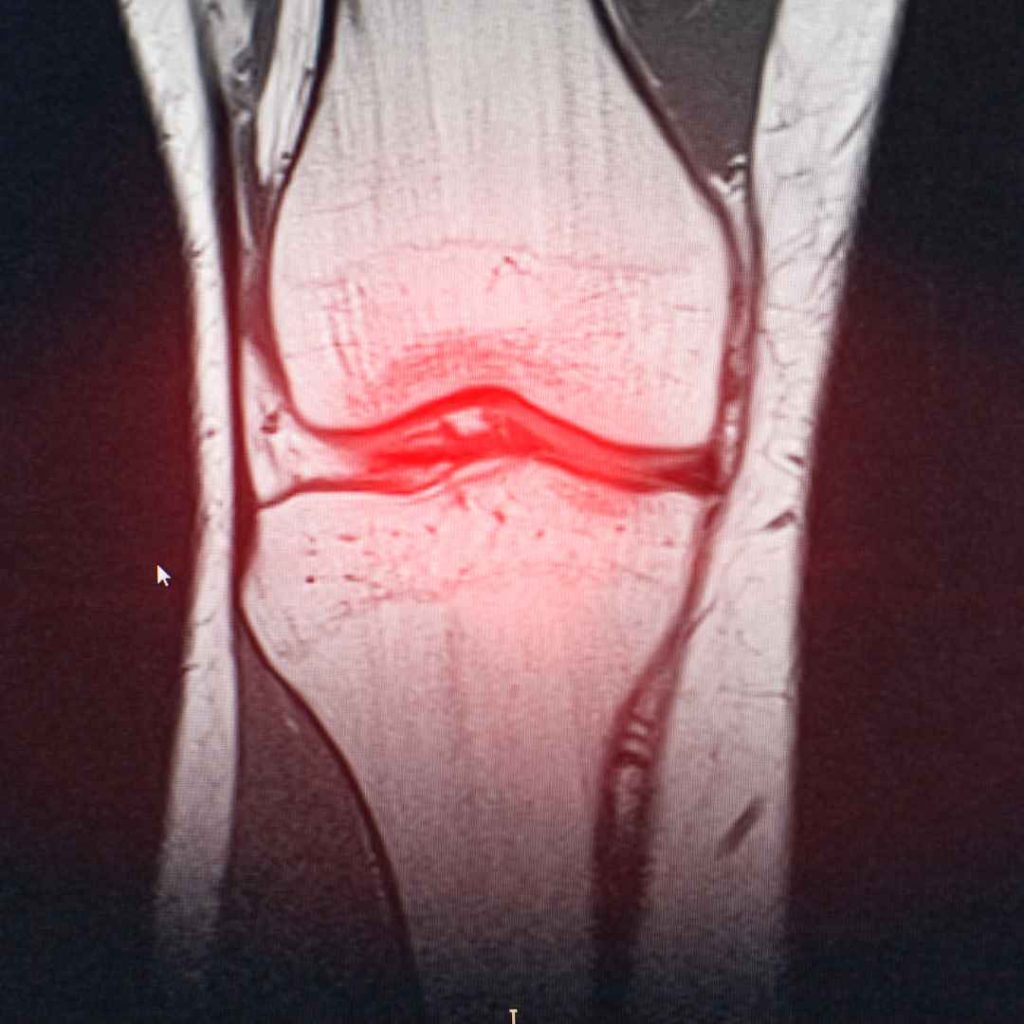

Nyeri sendi adalah rasa sakit, pegal, atau tidak nyaman yang muncul pada area persendian. Sendi itu sendiri merupakan bagian tubuh yang menghubungkan dua tulang, seperti lutut, siku, bahu, dan pergelangan tangan.

Menurut laman Mayo Clinic, nyeri sendi (joint pain) bisa disebabkan oleh berbagai faktor, mulai dari cedera, penggunaan sendi berlebihan (overuse), hingga kondisi medis tertentu seperti asam urat dan osteoarthritis.

Radang sendi adalah kondisi peradangan yang terjadi pada satu atau lebih sendi. Dalam istilah medis, kondisi ini disebut arthritis. Berdasarkan penjelasan dari Badan Kesehatan Dunia (WHO), arthritis adalah gangguan muskuloskeletal yang menyebabkan peradangan pada sendi, ditandai dengan nyeri, bengkak, kaku, dan keterbatasan gerak.

Osteoarthritis adalah jenis radang sendi yang bersifat degeneratif, artinya terjadi akibat proses keausan dan kerusakan tulang rawan sendi secara bertahap. Tulang rawan berfungsi sebagai bantalan yang mencegah gesekan langsung antar tulang.

Ketika tulang rawan menipis atau rusak, tulang akan saling bergesekan dan memicu peradangan ringan hingga sedang.